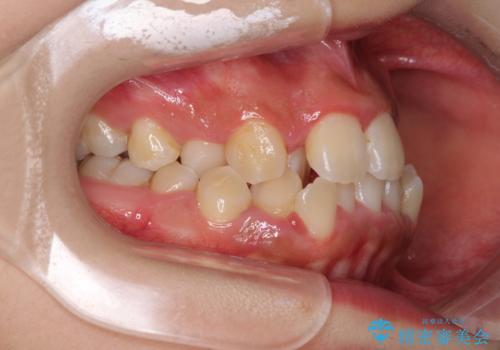

前後に重なった前歯 ワイヤー装置と急速拡大装置を併用したインビザライン矯正

- 前歯の著しい叢生とクロスバイトを気にして来院された患者様です。

叢生が強いため、一見すると抜歯矯正と判断したくなりますが、下顎臼歯が舌側に倒れていることから、上顎骨を側方拡大し、非抜歯矯正の可能性を検討することとしました。

急速拡大装置による上顎骨の側方拡大が思った以上にうまくいき、非抜歯での矯正が可能となりました。

内側に倒れていた下顎の臼歯は起き上がり、清掃性も大幅に改善されました。